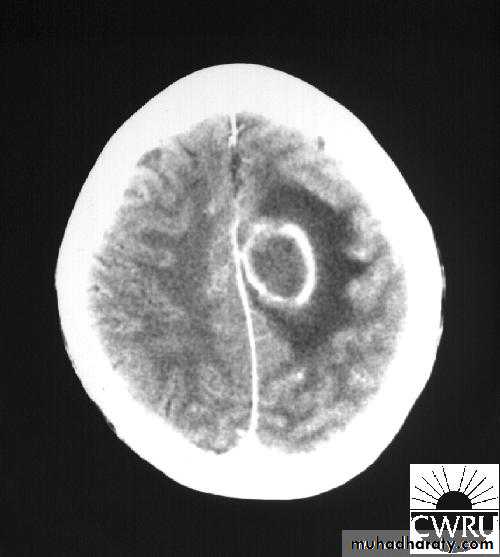

Stereotactic Aspiration of Brain Abscess

د.عبدالرحمن